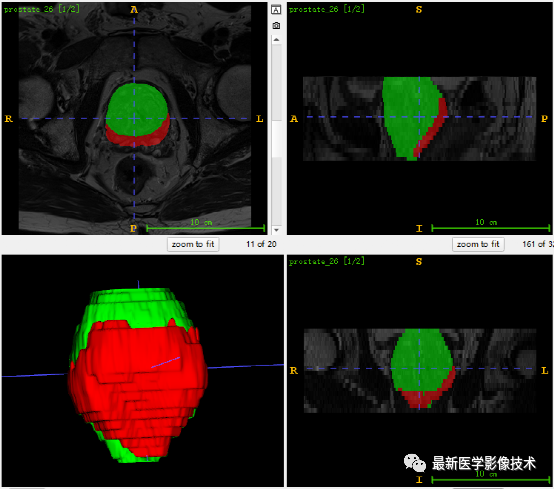

5、验证集分割结果

左边是金标准结果,右边是网络预测结果。